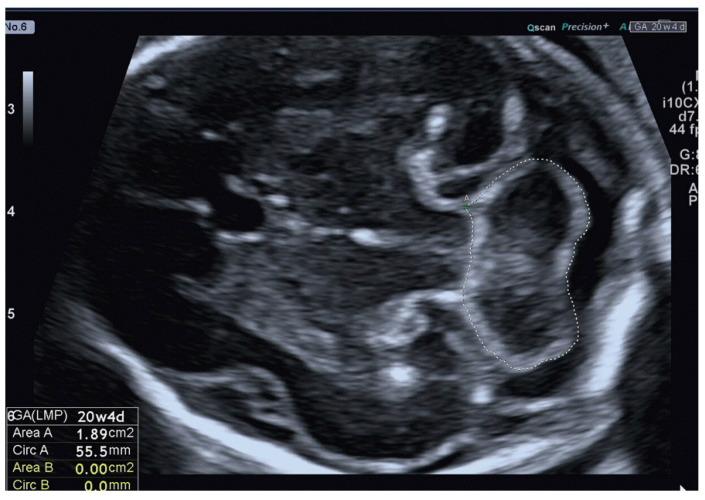

This is a prospective cross-sectional analysis of 252 normal singleton pregnancies, ranging from 13 to 39 weeks of gestation. The operator performed measurements of the fetal cerebellar area in the transverse plane using 2D-US. The relationship between cerebellar area and gestational age (GA) was determined through regression equations.

A significant, strong positive correlation was investigated between the cerebellar area with GA (r-value = 0.89), and a positive correlation indicates that with increasing GA, the cerebellar area increased in all the participants of the study. Several 2D-US nomograms of the normal cerebellar area were provided, and an increase of 0.4% in the cerebellar area each week of GA was reported.

这是一项对252例单胎正常妊娠进行的前瞻性横断面分析,妊娠周数为13至39周。操作人员使用二维超声在横切面上测量胎儿小脑区域。通过回归方程确定小脑区域与孕周(GA)之间的关系。

研究发现小脑区域与孕周之间存在显著的强正相关(r值 = 0.89),正相关表明随着孕周增加,研究中所有参与者的小脑区域均增大。提供了几张正常小脑区域的二维超声列线图,并报告了孕周每增加一周小脑区域增加0.4%。